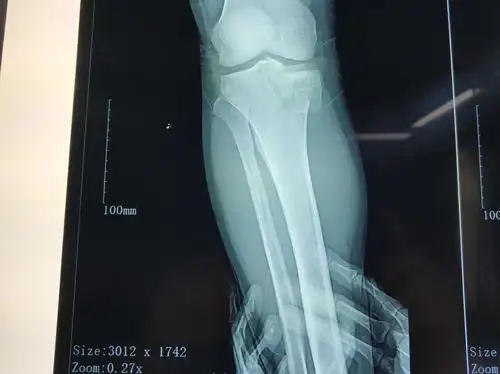

胫骨内侧髁骨折

右脚内踝骨折,有uu帮忙看看这个伤的严重吗